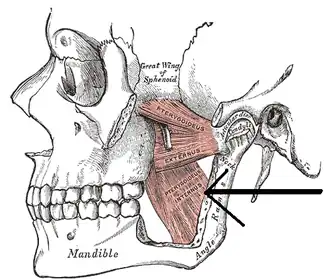

The pterygoidei; the zygomatic arch and a portion of the ramus of the mandible have been removed. (Internus is visible at center bottom.) | |

The medial pterygoid muscle consists of two heads. The bulk of the muscle arises as a deep head from just above the medial surface of the lateral pterygoid plate. The smaller, superficial head originates from the maxillary tuberosity and the pyramidal process of the palatine bone.

Its fibers pass downward, lateral, and posterior, and are inserted, by a strong tendinous lamina, into the lower and back part of the medial surface of the ramus and angle of the mandible, as high as the mandibular foramen. The insertion joins the masseter muscle to form a common tendinous sling which allows the medial pterygoid and masseter to be powerful elevators of the jaw.